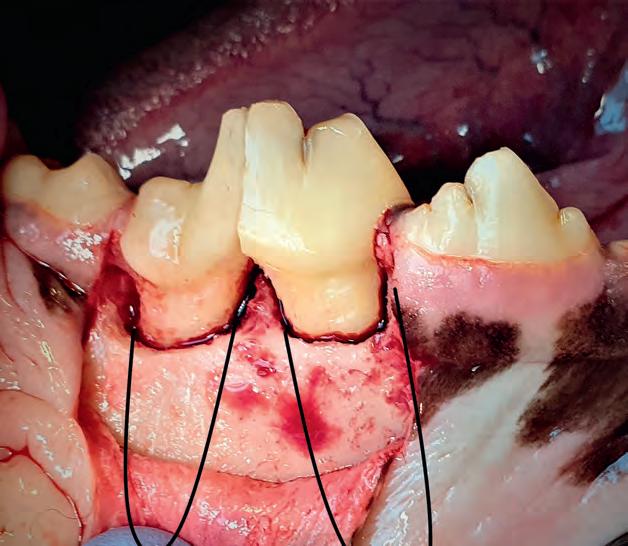

Met het verwijderen van de afgebroken tand of kies is het probleem van de infectie opgelost. Een snijtand verwijderen zal voor een hond geen grote gevolgen hebben. Een belangrijke knipkies of een hoektand wil je liever behouden voor de hond. De knipkiezen zijn de grootste kiezen in de boven- en onderkaak, waarmee een hond zijn voedsel kapot ‘knipt’. Bedenk ook dat een extractie van een knipkies of hoektand (met lange wortel) een grote ingreep is voor de hond. Deze worden niet ‘even’ met een tang eruit getrokken, zoals bij de humane tandarts een kies bij de mens getrokken wordt. Als bij de hond een kies of hoektand met een tang getrokken zou worden, dan zou de kroon (bovenste gedeelte van de tand) afbreken en de geinfecteerde wortel(s) in de kaak achterblijven. Daarom moeten gebitselementen bij de hond kaakchirurgisch verwijderd worden. Dit wordt gedaan door eerst een tandvleesflap te creëren, waarna het kaakbot rondom de wortels deels weggeboord wordt. De kroon van de kies wordt in tweeën geboord zodat de wortels stuk voor stuk verwijderd kunnen worden. Met gebruik van verschillende instrumenten worden de wortels voorzichtig los gemaakt en daarna volledig verwijderd. Tot slot wordt de wond spanningsvrij dicht te hechten met behulp van de tandvleesflap. Hiermee wordt de opening van de verwijderde kies of hoektand secuur afgesloten.

Kaakchirurgische extractie van de grote knipkies in de onderkaak, na het klieven van de kroon. Met zwarte lijnen zijn de wortels van deze kies weergegeven.